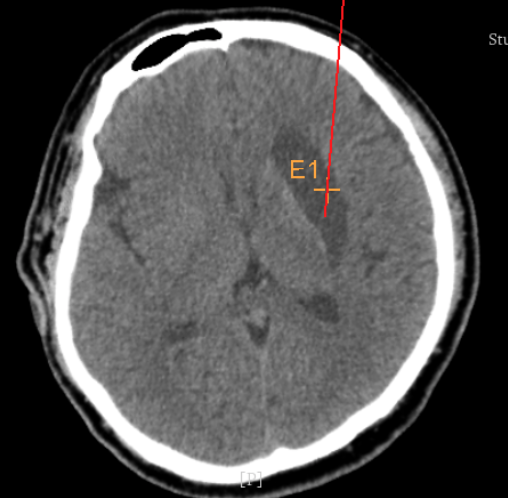

術(shù)前CT:血腫已經(jīng)液化,但仍有占位效應(yīng)

術(shù)前韓帥醫(yī)生使用“睿米”制定手術(shù)規(guī)劃

手術(shù)規(guī)劃在機(jī)器人軟件上制定完成